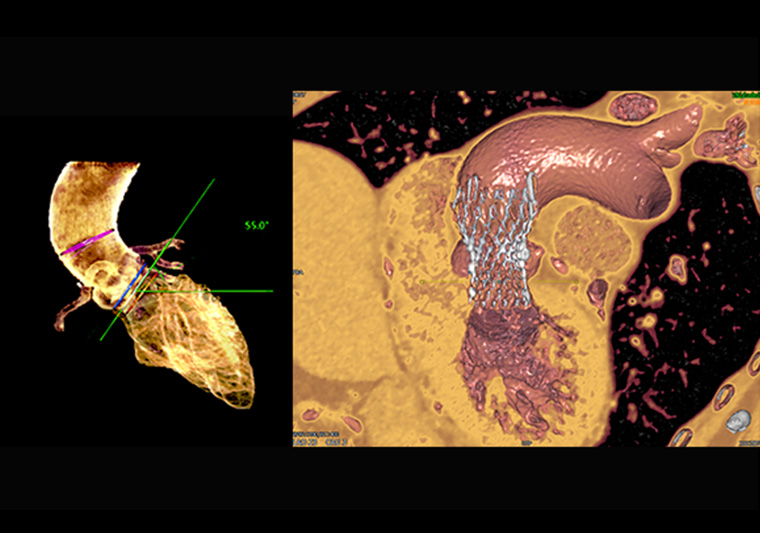

ANYTHINK 经导管主动脉瓣膜置换术分析系统